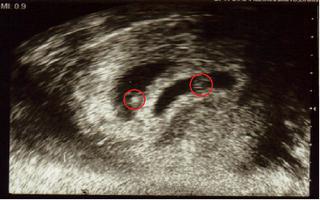

Adrous, tak specialne pre teba jedna specialna fotecka 🙂

sylvi utz je krásny...gratulujem

sylvi pekne machulky 😵 a kedy si bola na utz?

sylvi, krasna fotocka 🙂